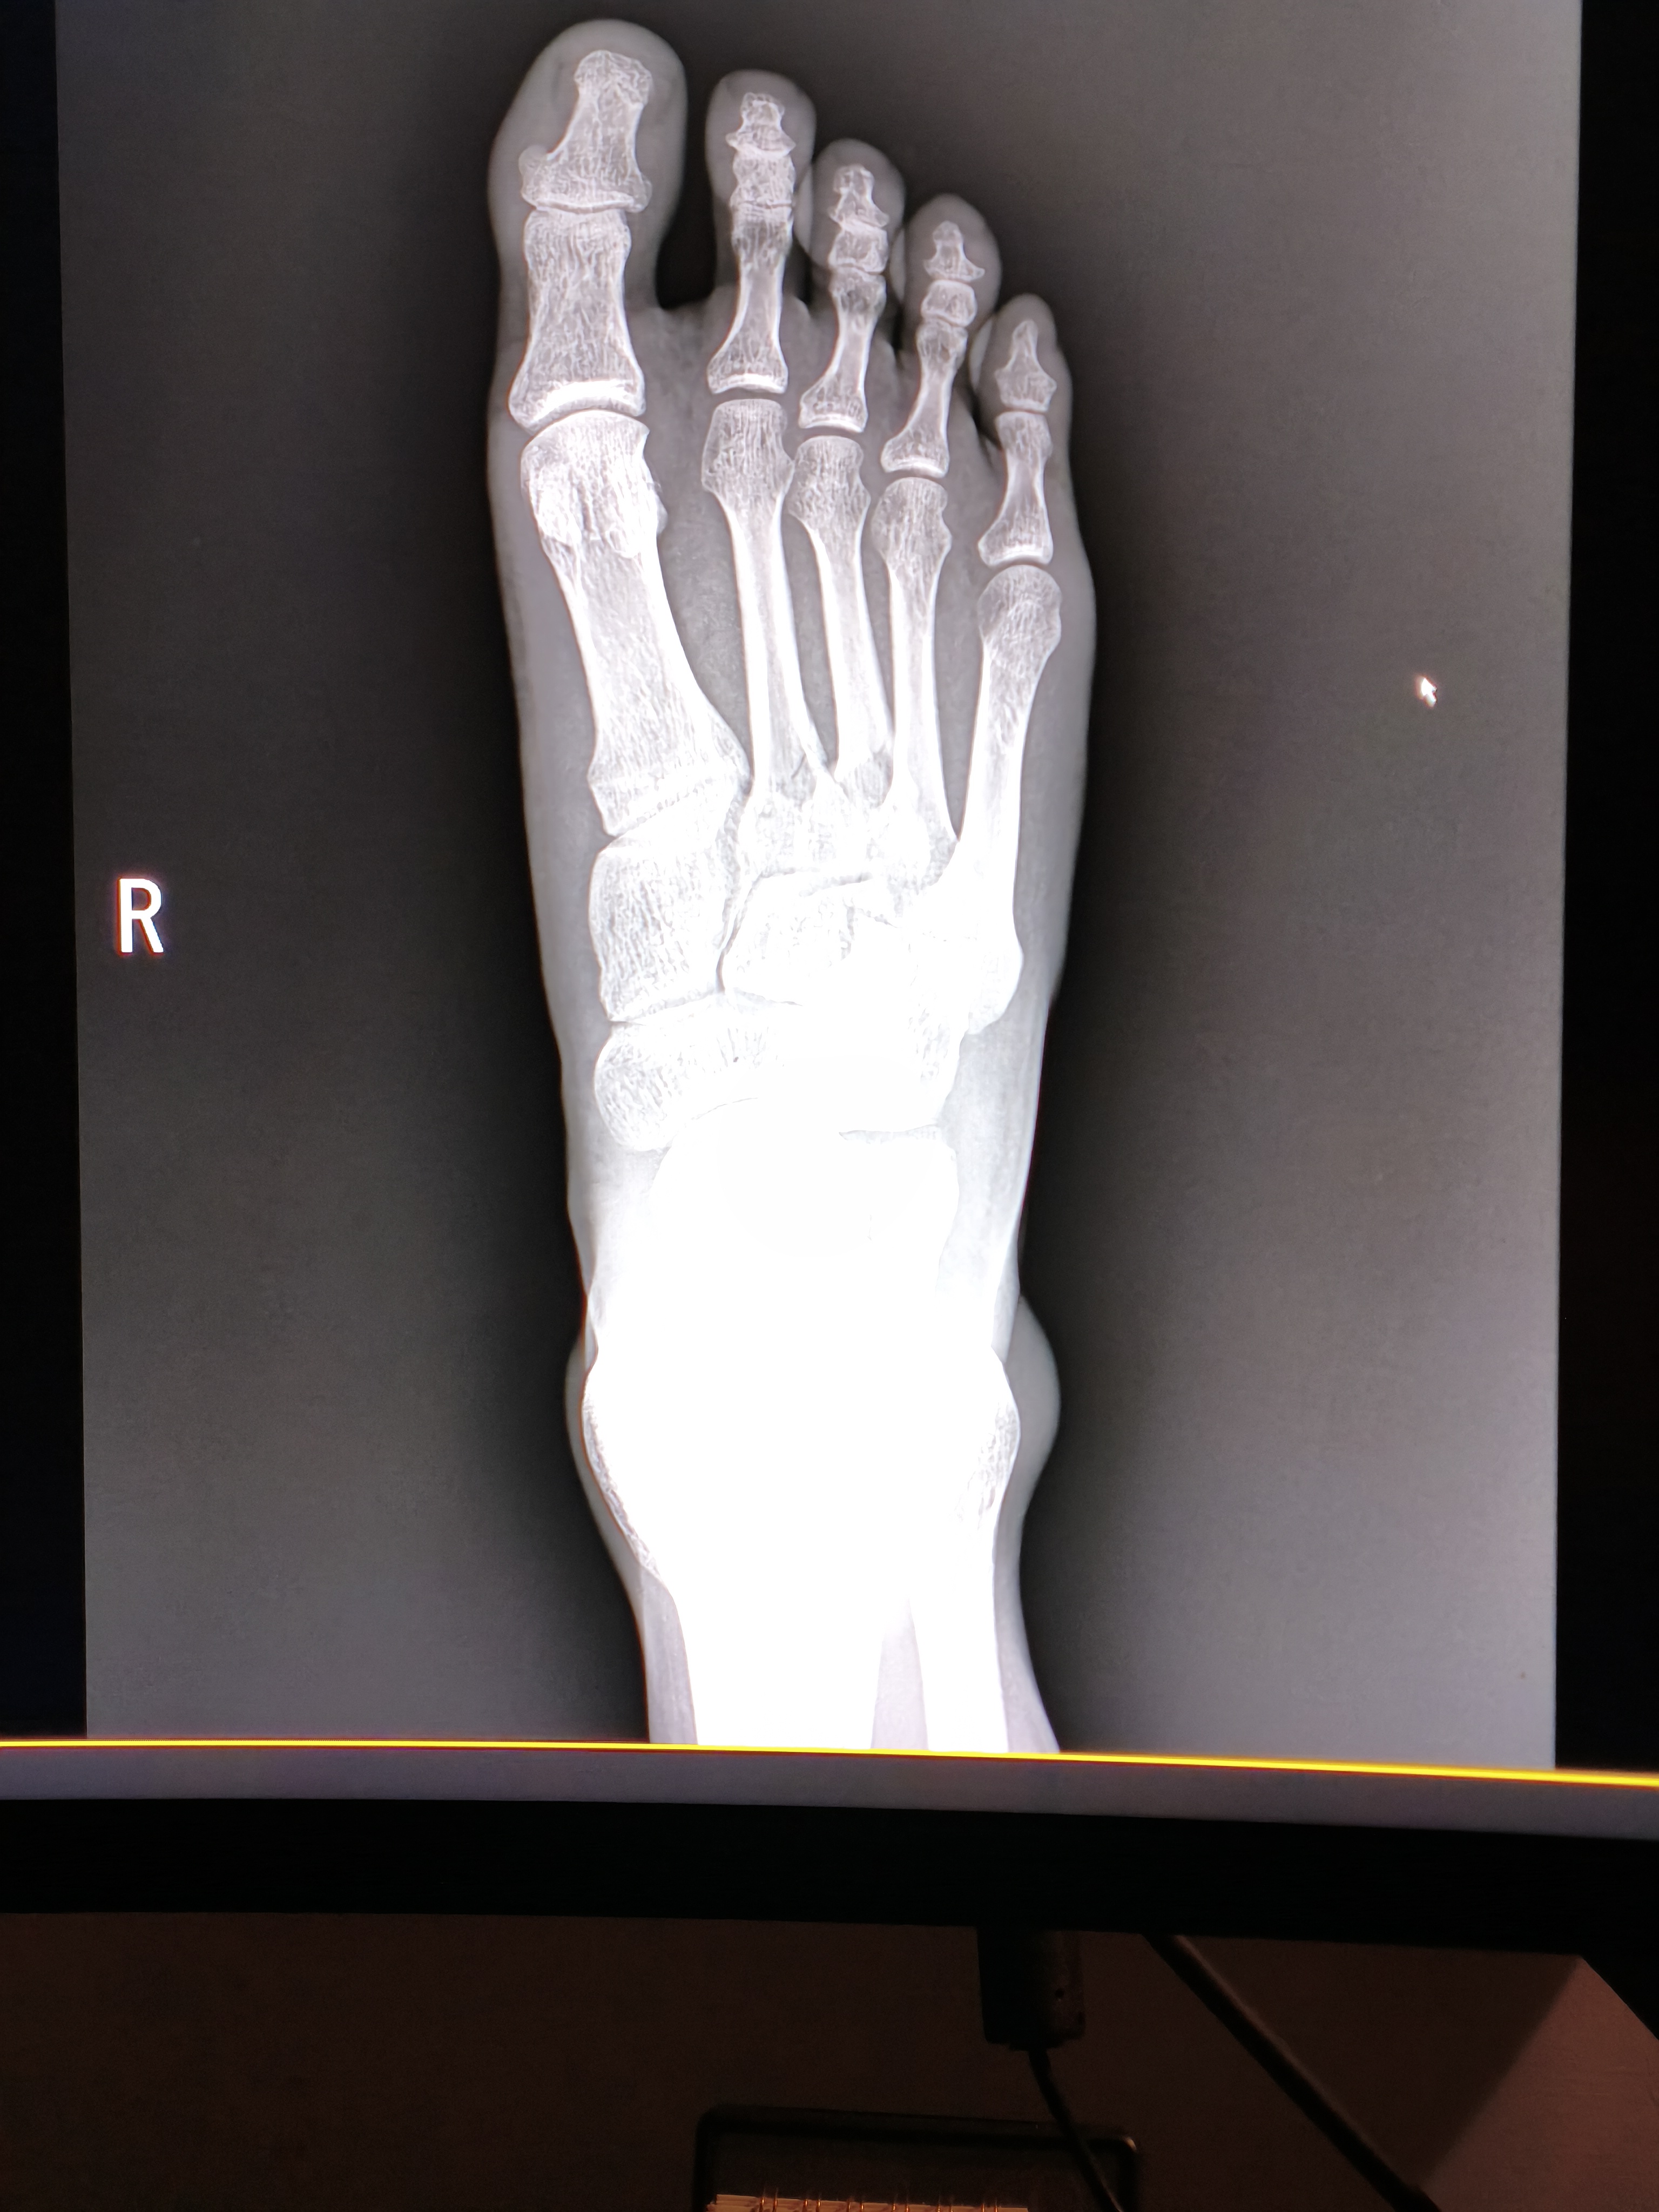

지난주 토요일 발등 골절 판정을 받아 두군데 진료받았는데 병원비가 너무 비싸서 수술을 미뤄도 될 상황인지 알고 싶습니다.

예후가 안좋은 부위라는데 수술비로 다 나가면 생활이 안되어서요.

실손보험들어놓으신것있으면 좋을텐데 걱정되는군요, 수술하시는게 맞습니다 아니면 평생 신경쓰이게 불편할가능성이 높거든요

발등 골절은 방치 시 보행 장애 등 후유증이 크므로,

긴급복지지원이나 재난적 의료비 제도를 통해 비용 부담을 줄여서라도

골든타임 내 수술받으시는 것이 나중을 위해 훨씬 안전합니다.